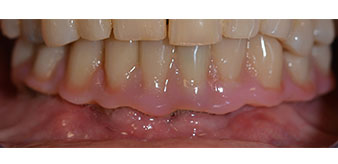

Tras esto, se realizan la impresión y el registro de la mordida para que el protésico dental pueda empezar inmediatamente con la elaboración de la prótesis provisional, cuya implantación se realiza el mismo día (figs. 17 y 18).

Una vez transcurrido el tiempo necesario para la integración ósea, puede llevarse a cabo la impresión definitiva del implante para realizar la prótesis definitiva de manera acorde (figs. 19 y 20). En este paso, el responsable del tratamiento y el paciente pueden decidir conjuntamente si es preferible un revestimiento cerámico o plástico y una estructura de zircón o de metal. En este caso, dado que el pronóstico de la dentición del maxilar superior era poco claro y la pieza dental 24 estaba elongada, el equipo del Dr. Pascu se decidió por un revestimiento de plástico, ya que, por lo general, es mucho más fácil de ajustar y puede adaptarse a la nueva situación del maxilar superior.